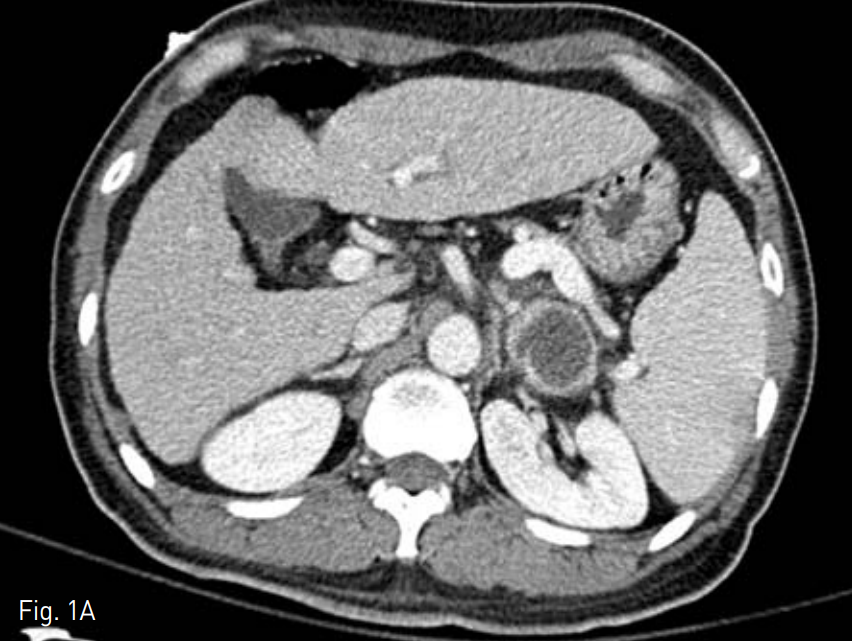

이후 발열은 관찰되지 않고 배액양이 5cc 이하로 감소하였으며 배액관을 통해 시행한 관조영술상 농양강이 허탈 되어 배액관을 제거하였다. 시술 1주일 후 촬영한 조영증강 전산화 단충촬영술에서 허탈된 농양강과 함께 비장에 경색으로 의심되는 쐐기 모양의 저음영의 영역이 관찰되었으나(Fig. 4A) 3개월 뒤 시행한 검사에서 저음영의 영역은 사라진 것을 관잘할 수 있었다(Fig. 4B).

B. Contrast enhanced CT scans 3 months after the procedure shows disappearance of low density lesion in the spleen.